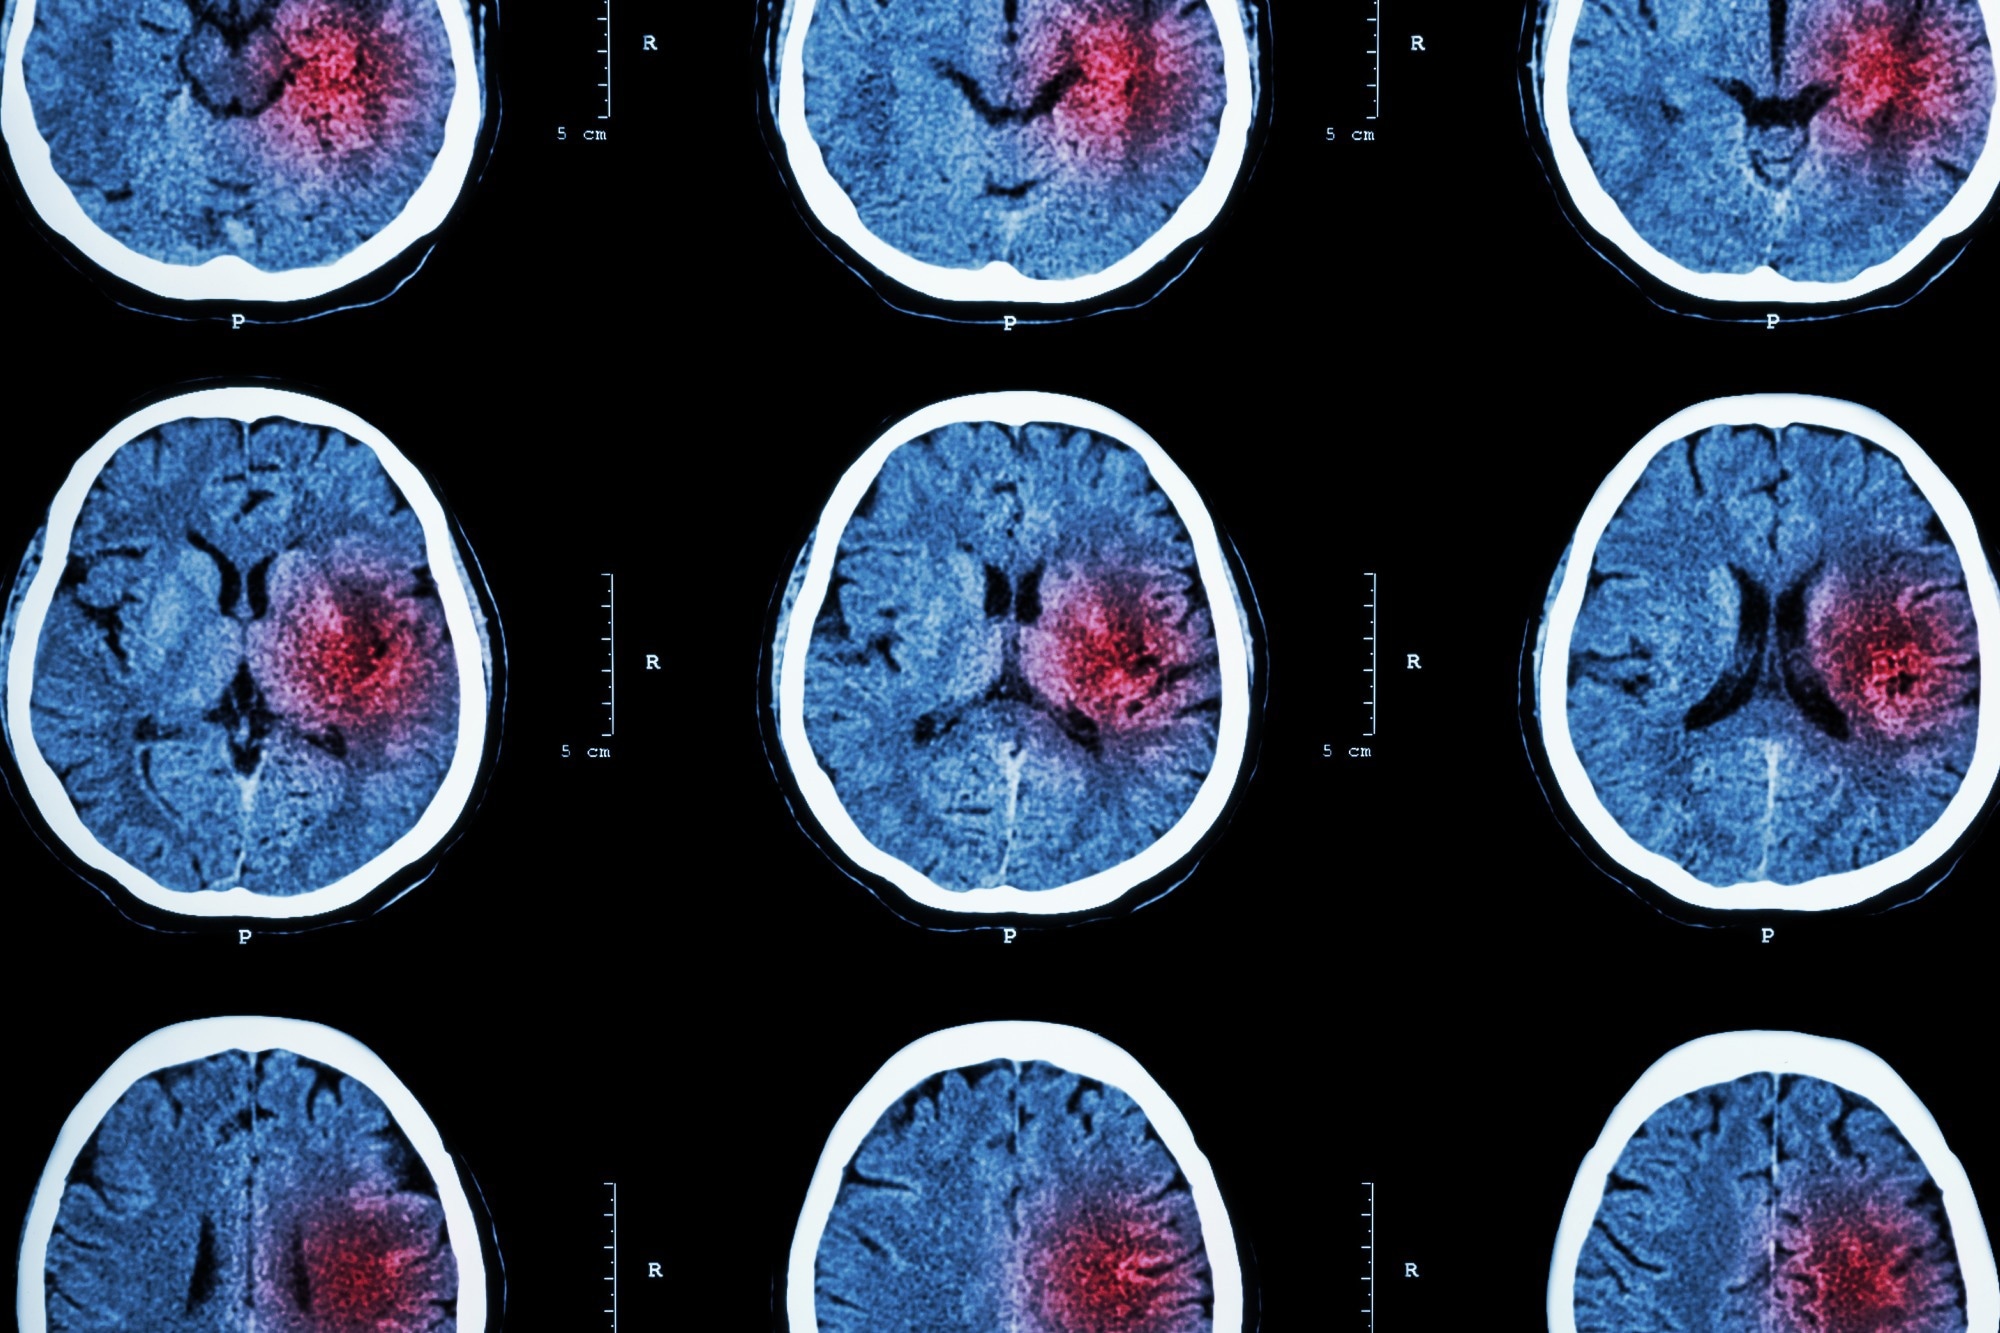

A stroke occurs when a blood vessel that carries oxygen and nutrients to the brain is either blocked by a clot or bursts. Therefore, there are two types of stroke: ischemic and hemorrhagic.

Ischemic strokes – which are the most common and account for 87% of all cases – occur when a blood clot travels to a vessel in the brain and cuts off the blood supply. This prevents brain tissue from getting oxygen and nutrients, and brain cells can begin to die in minutes.

The other type of stroke, hemorrhagic, are often less common than ischemic strokes but can be more severe. These types of strokes are caused by a brain aneurysm burst or rupture of weakened blood vessels.

Image Credit: Inspiring/Shutterstock